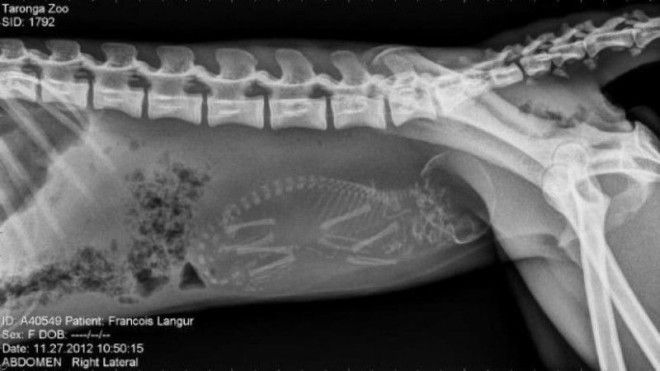

12. Беременная обезьяна